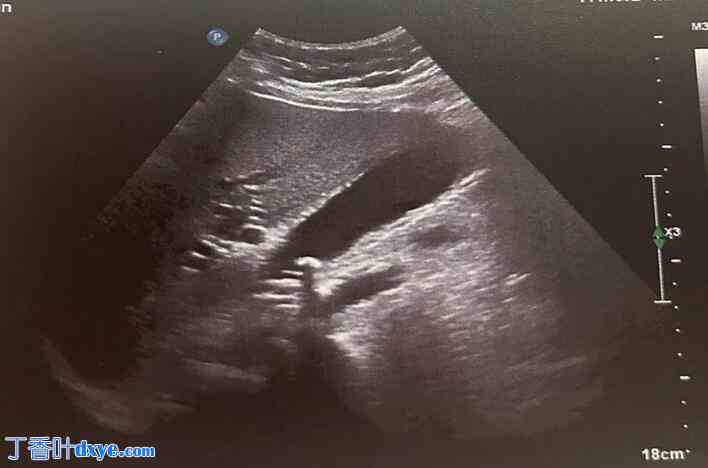

图 1.

腹部超声检查显示胆囊未扩张,胆囊壁薄,内容物为多结石,胆囊壁上无异位实质。